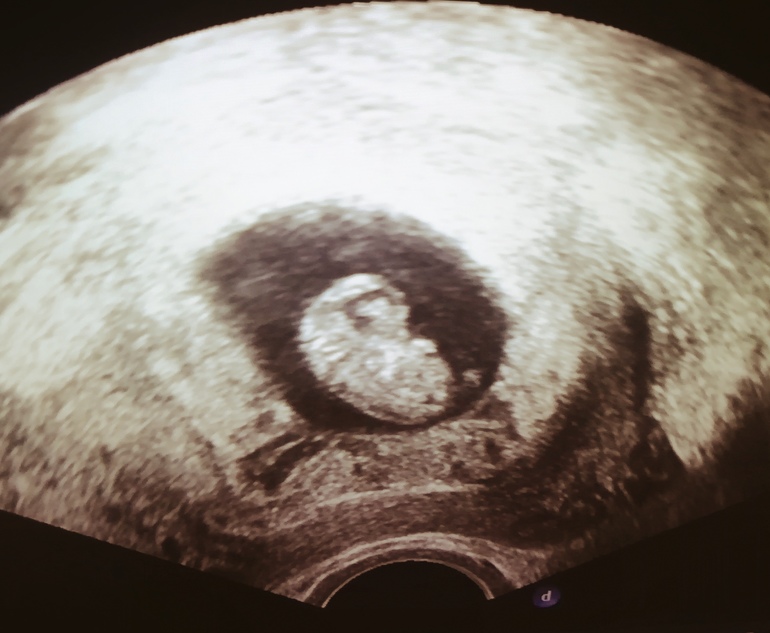

Второе узи! Фото

ЗачатиеРешила я все-таки перед анализом на определение пола сделать узи. Узистка на благо попалась с 10ти летним опытом работы на скрининге, все рассказала, все хорошо, тьфу тьфу тьфу. Сняла короткое видео как бьётся сердечко.

Ктр 2, 49 опять меньше, но сказала узистка что это норма, значит позже зачатие, оно так и было на 18-19дц. Пишет мне с таким ктр 8нед 5 дней, а я смотрю по таблице 9 нед 3 дня??????